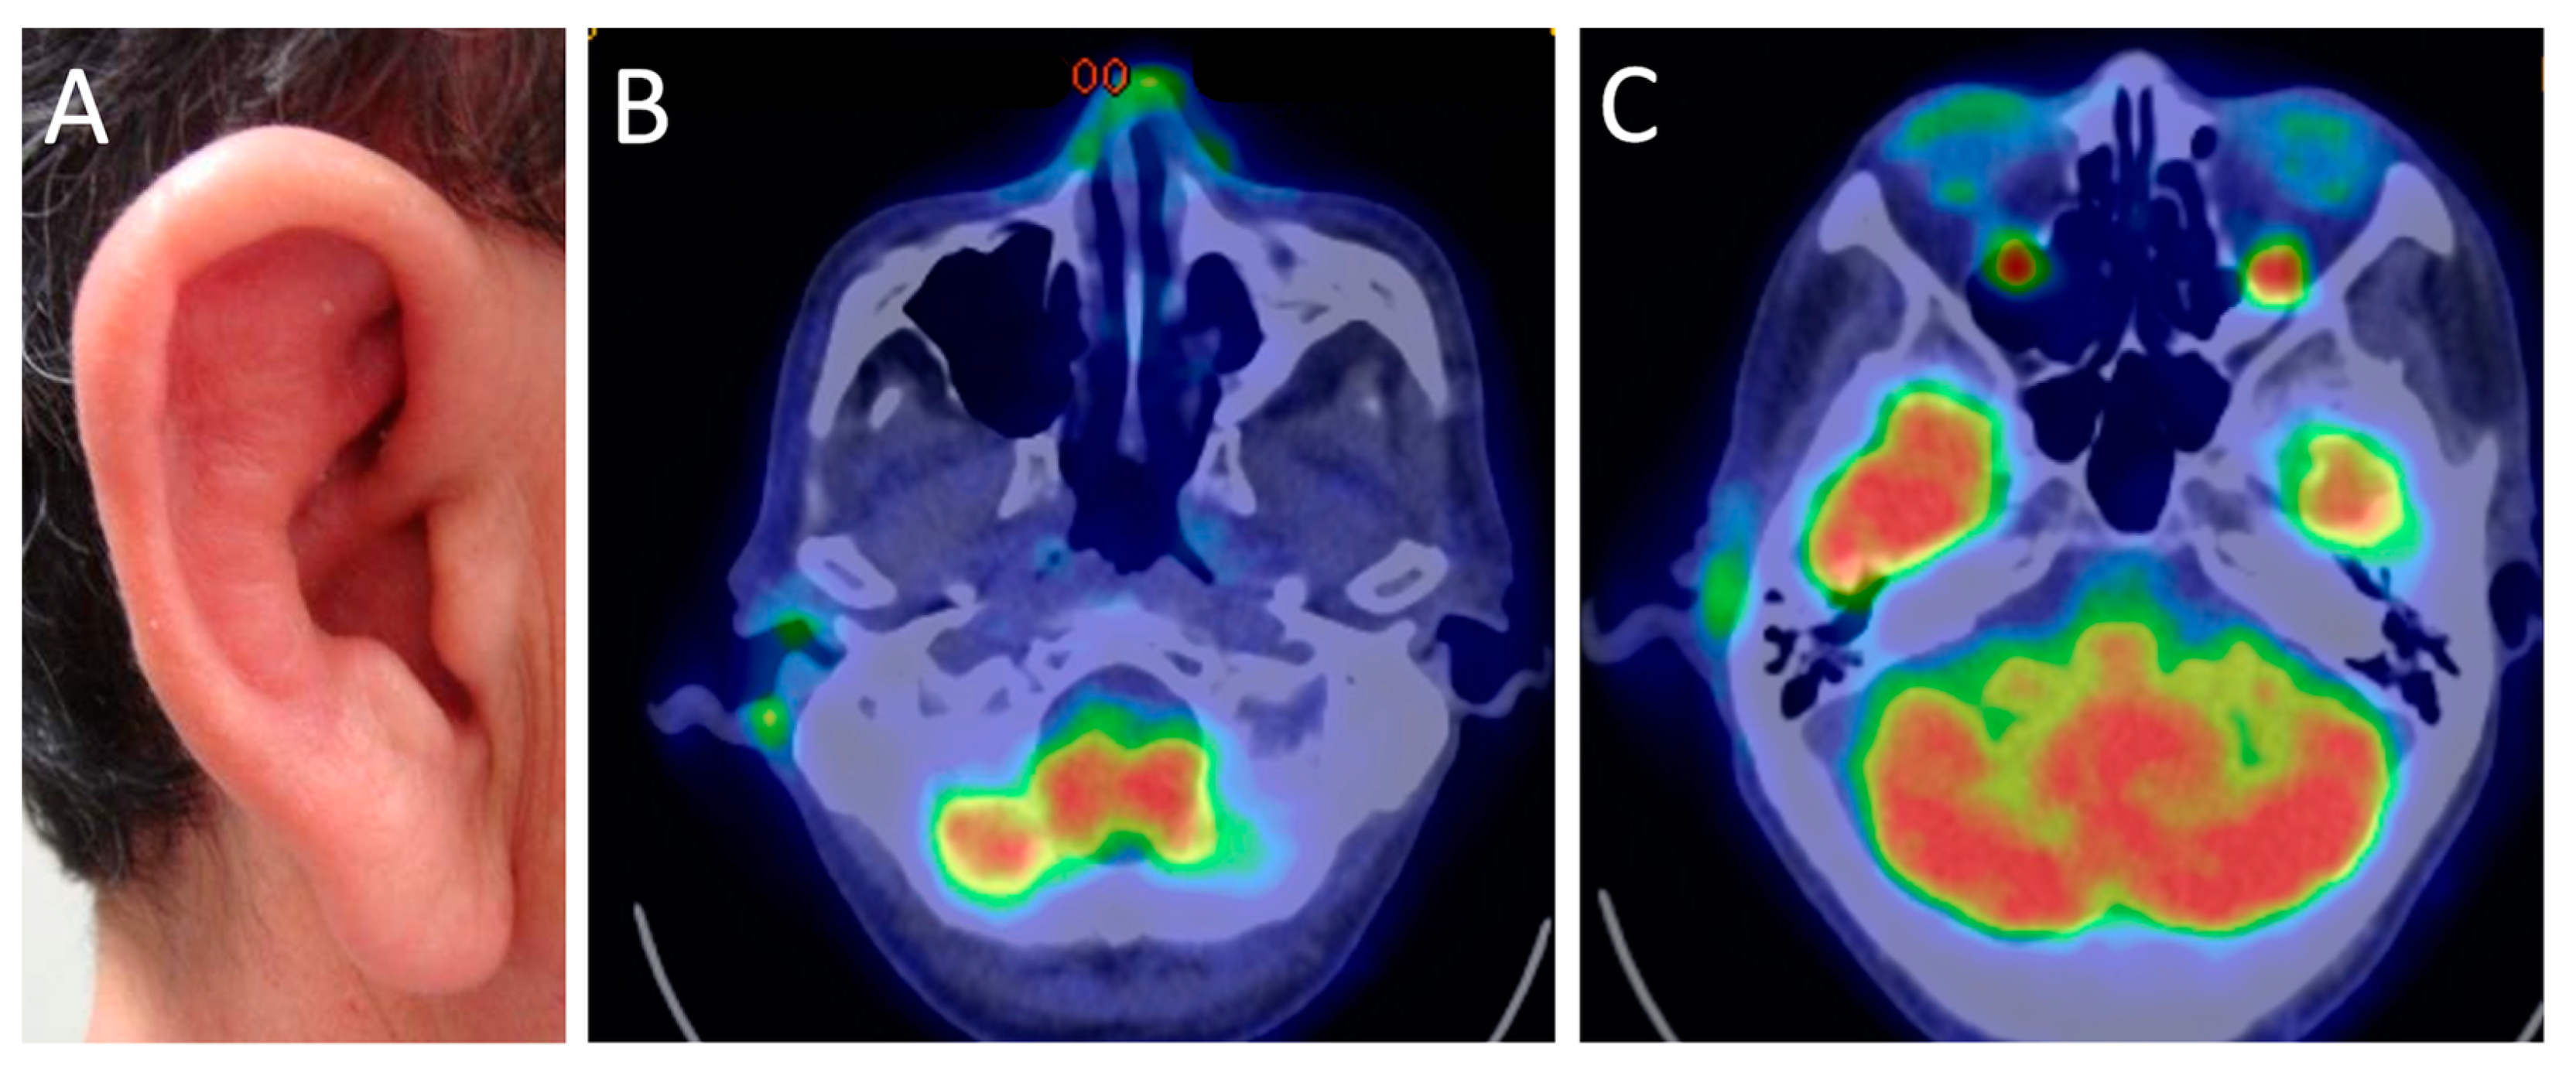

- Kubota, K.; Yamashita, H.; Mimori, A. Clinical Value of FDG-PET/CT for the Evaluation of Rheumatic Diseases: Rheumatoid Arthritis, Polymyalgia Rheumatica, and Relapsing Polychondritis. Semin. Nucl. Med. 2017, 47, 408–424. [Google Scholar] [CrossRef]